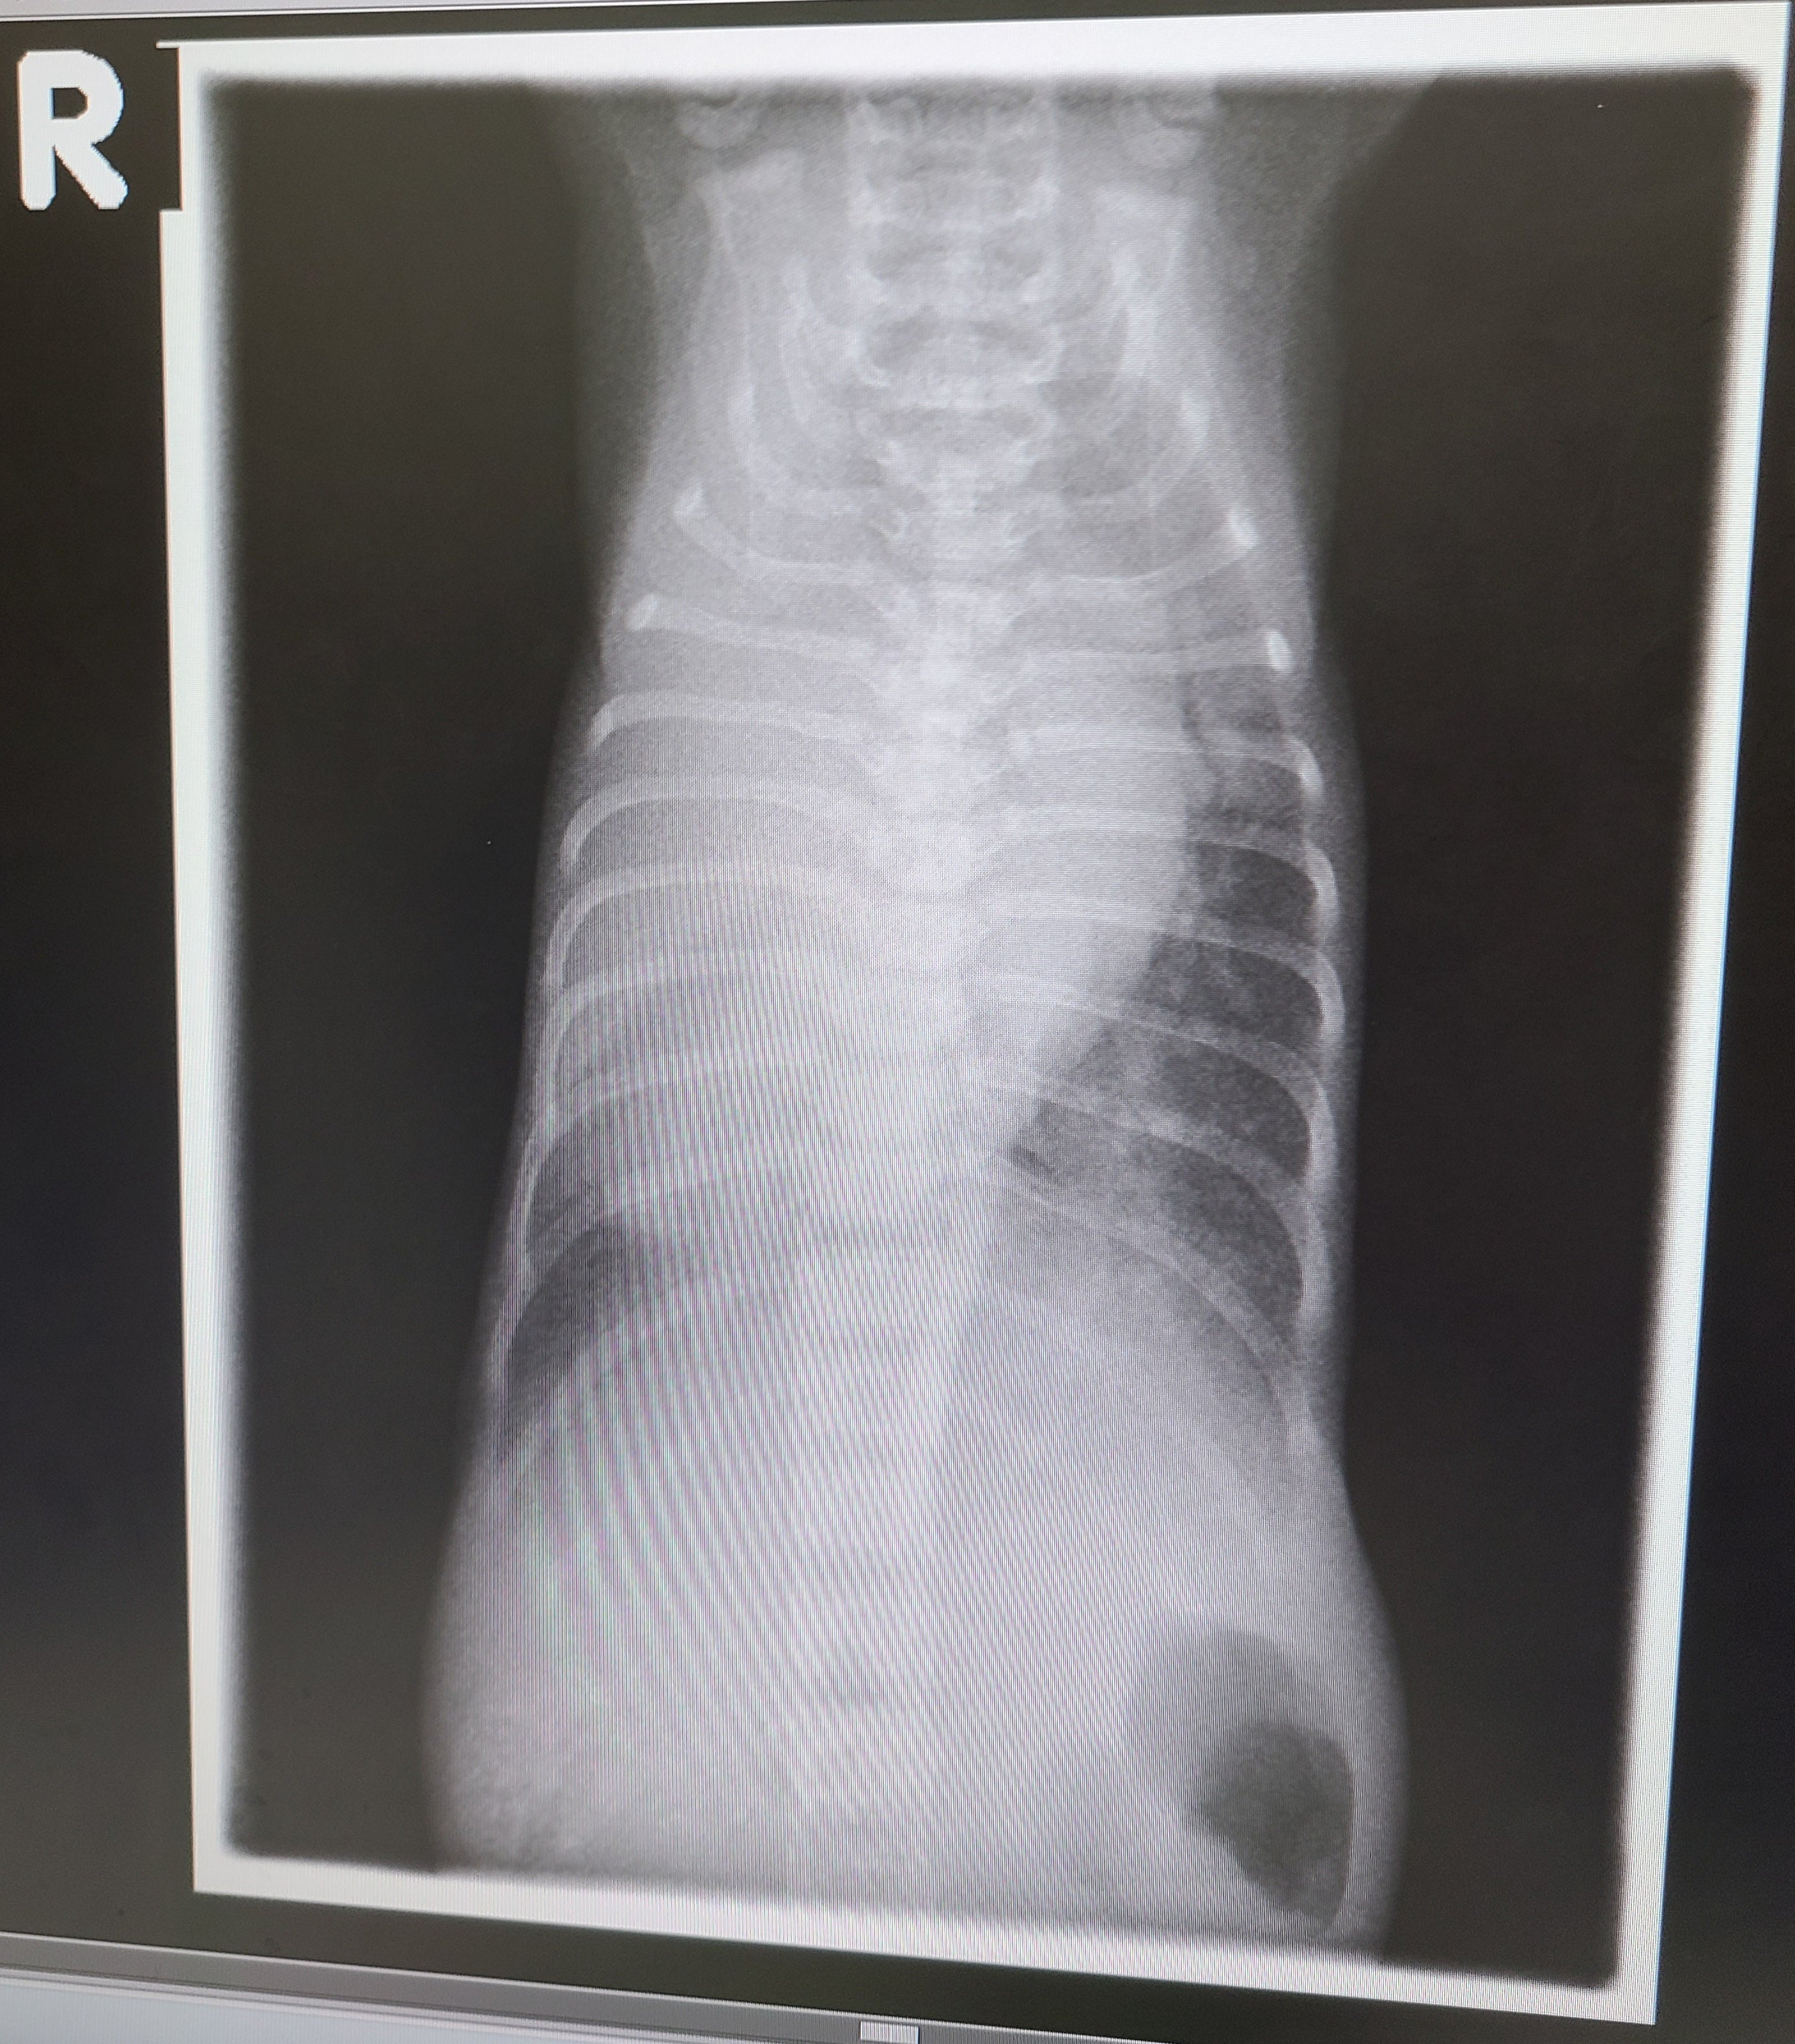

「まずレントゲンを見てもらいたいのですが…」

循環器科なのに背中側から撮るというのはなんらか意味があるのだろう…

ん? R…?

右ってこと?

「これ、バンザイした状態でお腹側から撮っているのですが…」

仰け反ると同時に、ひーっ!とまた大きめの声が出ました。

「そうなんです。心臓の下の先端が右にあります。」

まじか…逆位(ぎゃくい)している…

身体の中の内臓が左右逆に出来ている可能性が高い。

部分逆位といって、横隔膜から上が逆位しているだけの可能性もあるが、空腹時の胃のガスの位置的に、全身逆位の可能性あり。とのこと。

やはり、心臓の左側の壁より、右側の壁が厚い。

心臓は右心系より左心系の方が筋肉が分厚く出来ているので、右側が分厚いということは、左心系が右側にあるということ。

「レントゲンの結果を見てもわかるように、胸骨が若干内側にへこんでいます。

漏斗胸とまではいかないですが。

横隔膜が目一杯息を吸おうとしても、胸骨が胸腔(きょうくう)を狭くしてしまっているので、酸素と二酸化炭素の交換が多少上手く出来ていない可能性が高いです。」

早速胸部レントゲンと心エコーの結果を見せてもらいます。

前回と大きく目立って変わっているところはなく。

胸腔(きょうくう)の右下に見えている心臓の端っこ(下部)、先生の経験から見ると、なんとなく腹部の内臓が横隔膜ヘルニア(胸部と腹部の間にある横隔膜に穴が空いている)で胸腔に飛び出してしまっているようにも見える…と。

心臓と飛び出した内臓が隣り合ってひとつの臓器に見えているのかも?と。

それならたしかに苦しいに違いない。

肺があるはずのスペースに腹部の内臓があるのだから。

レントゲンでは影しか映らないので、そこにあるのが心臓なのか、横隔膜から飛び出してしまっている内臓なのかは、どちらも同じ色なので判断がつかず。